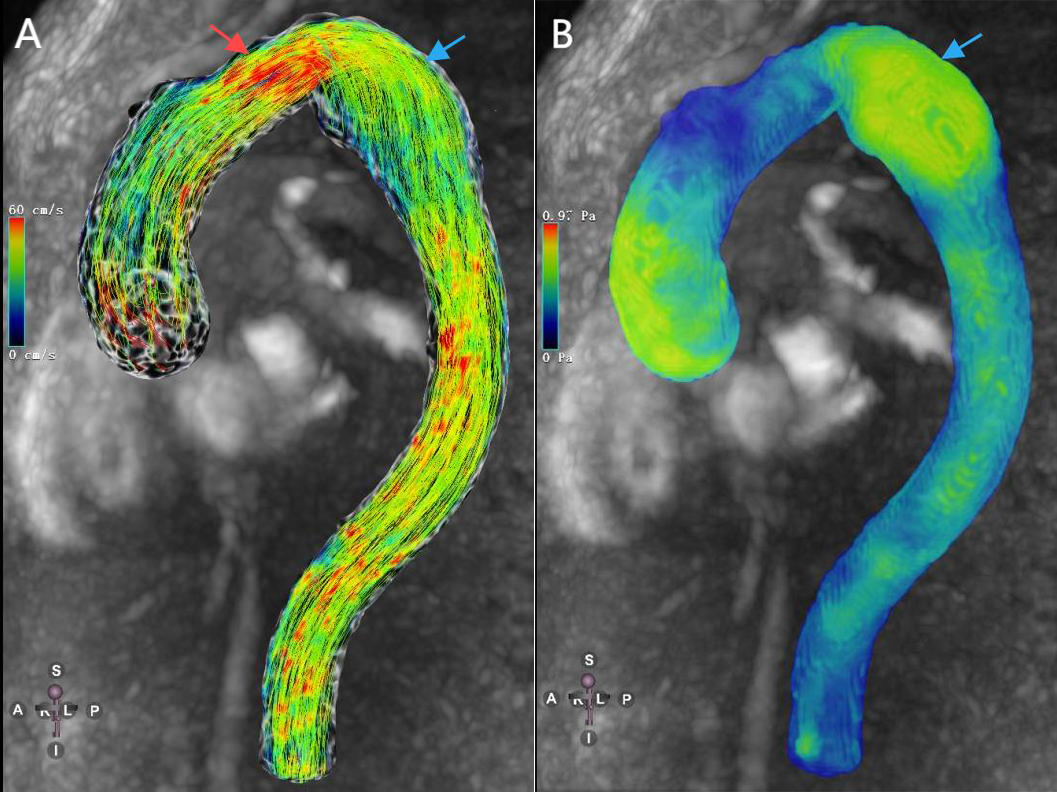

During aneurysm evolution, there are morphological and hemodynamic differences between aneurysms with different WSS, and both high and low WSS potentially contributing to aneurysm growth and rupture [67, 68]. Salmasi et al. [24] assessed the relationship between preoperative 4D Flow MRI images and postoperative tissue specimen characteristics in patients with ascending aortic aneurysms, finding that areas of high WSS were associated with aortic wall thinning, elastin abundance, and decreased smooth muscle cell counts. This suggests that degradation and thinning of the aneurysm wall are associated with hemodynamic impairment and high WSS (Fig. 2). Conversely, low WSS leads to inflammatory cell-mediated endothelial injury and apoptosis, with low and oscillating WSS areas being prone to plaque formation. This results in large, thick-walled aneurysms due to the combination of the inflammatory response and plaque buildup [69].

Fig. 2. A patient with descending aortic aneurysm. (A) 4D-flow-Image with streamlines demonstrates low velocity inside the thoracic aortic aneurysm (blue arrow) and high velocity around the aneurysm (red arrow). (B) 4D-flow-Image demonstrates high WSS inside the thoracic aortic aneurysm (blue arrow).

Aortic aneurysms often exhibit vortex or helical flow, with lesion areas showing low WSS and high OSI [25, 26, 60, 61]. These abnormal hemodynamics tend to promote aortic atherosclerosis, which in turn leads to progressive aortic dilatation and increases the risk of aneurysm rupture. Additionally, it has been found that RRT seems to be a more powerful predictor of hemodynamic changes in aortic aneurysms than the commonly used OSI [18], as it accounts for both the magnitude and direction of WSS.